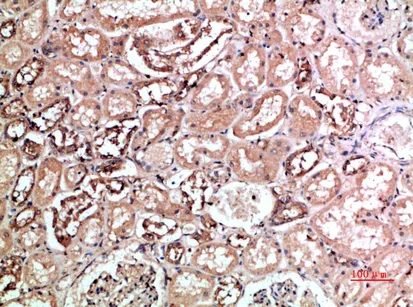

CD158f1/2 Rabbit Polyclonal Antibody

Cat: APRab08226